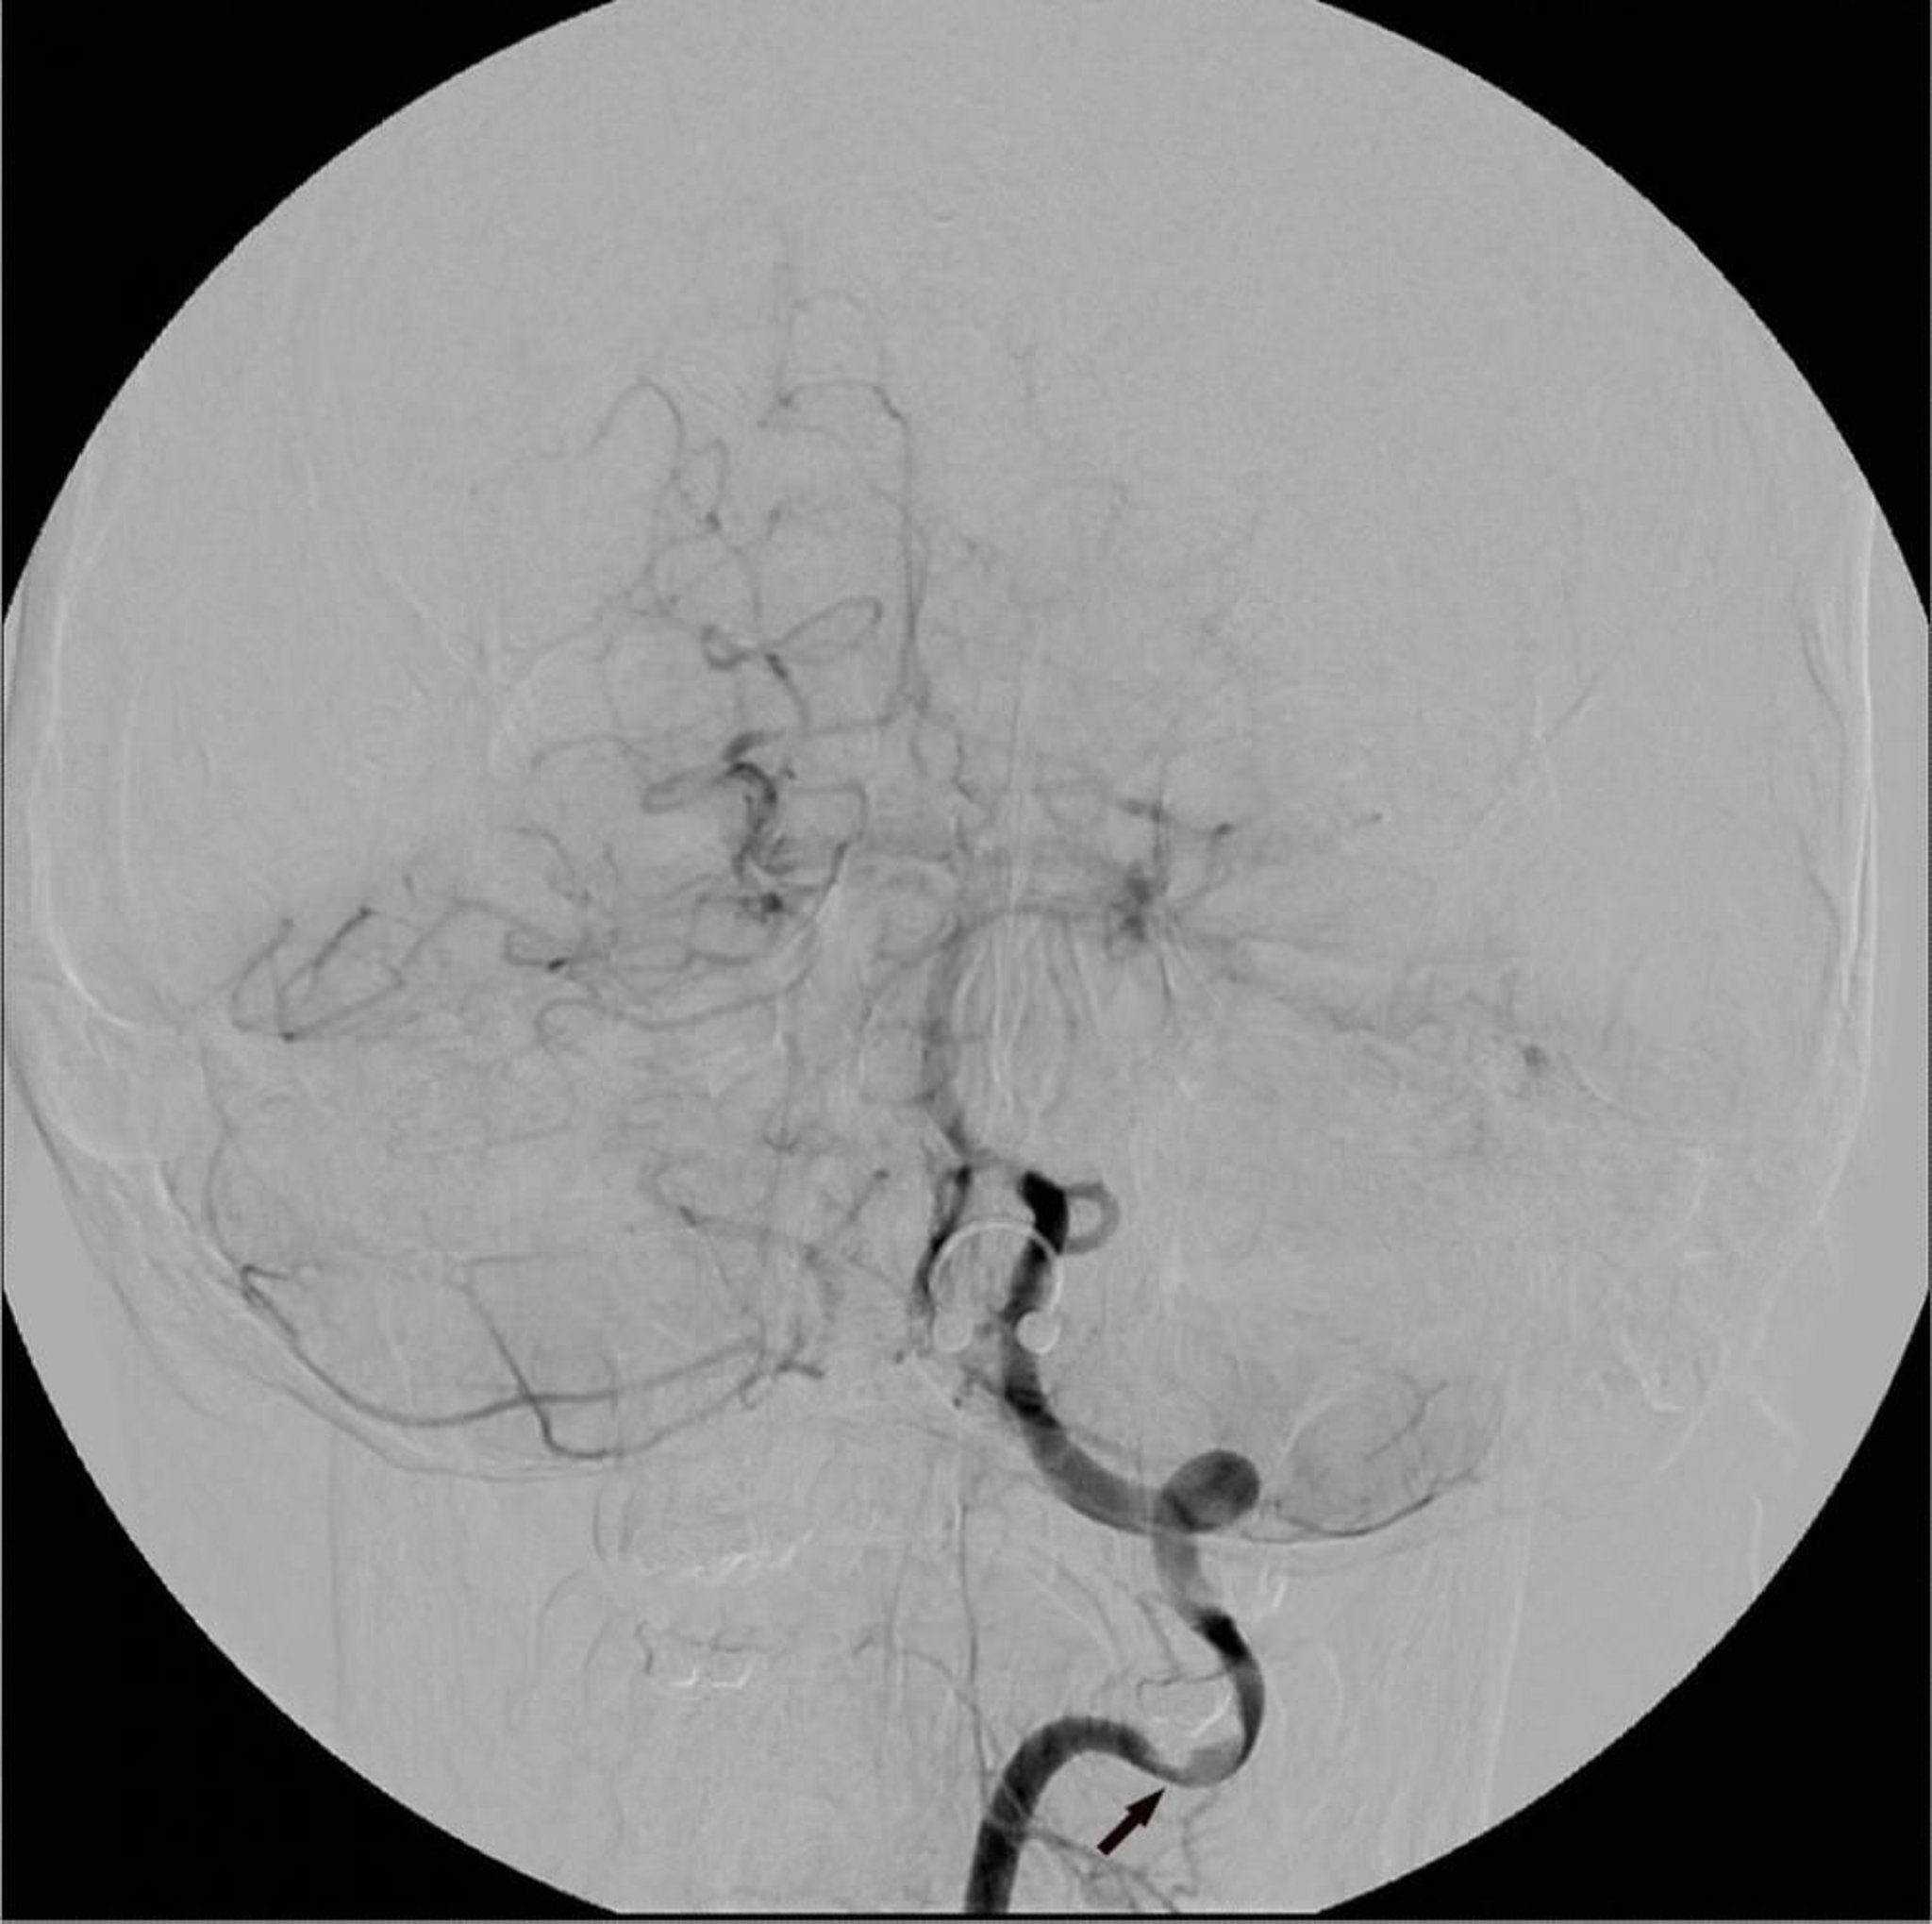

デジタルサブトラクション血管造影

この左椎骨動脈のデジタルサブトラクション血管造影(DSA)には,局所的な狭窄(矢印)が示されている。

Image courtesy of Hakan Ilaslan, MD.